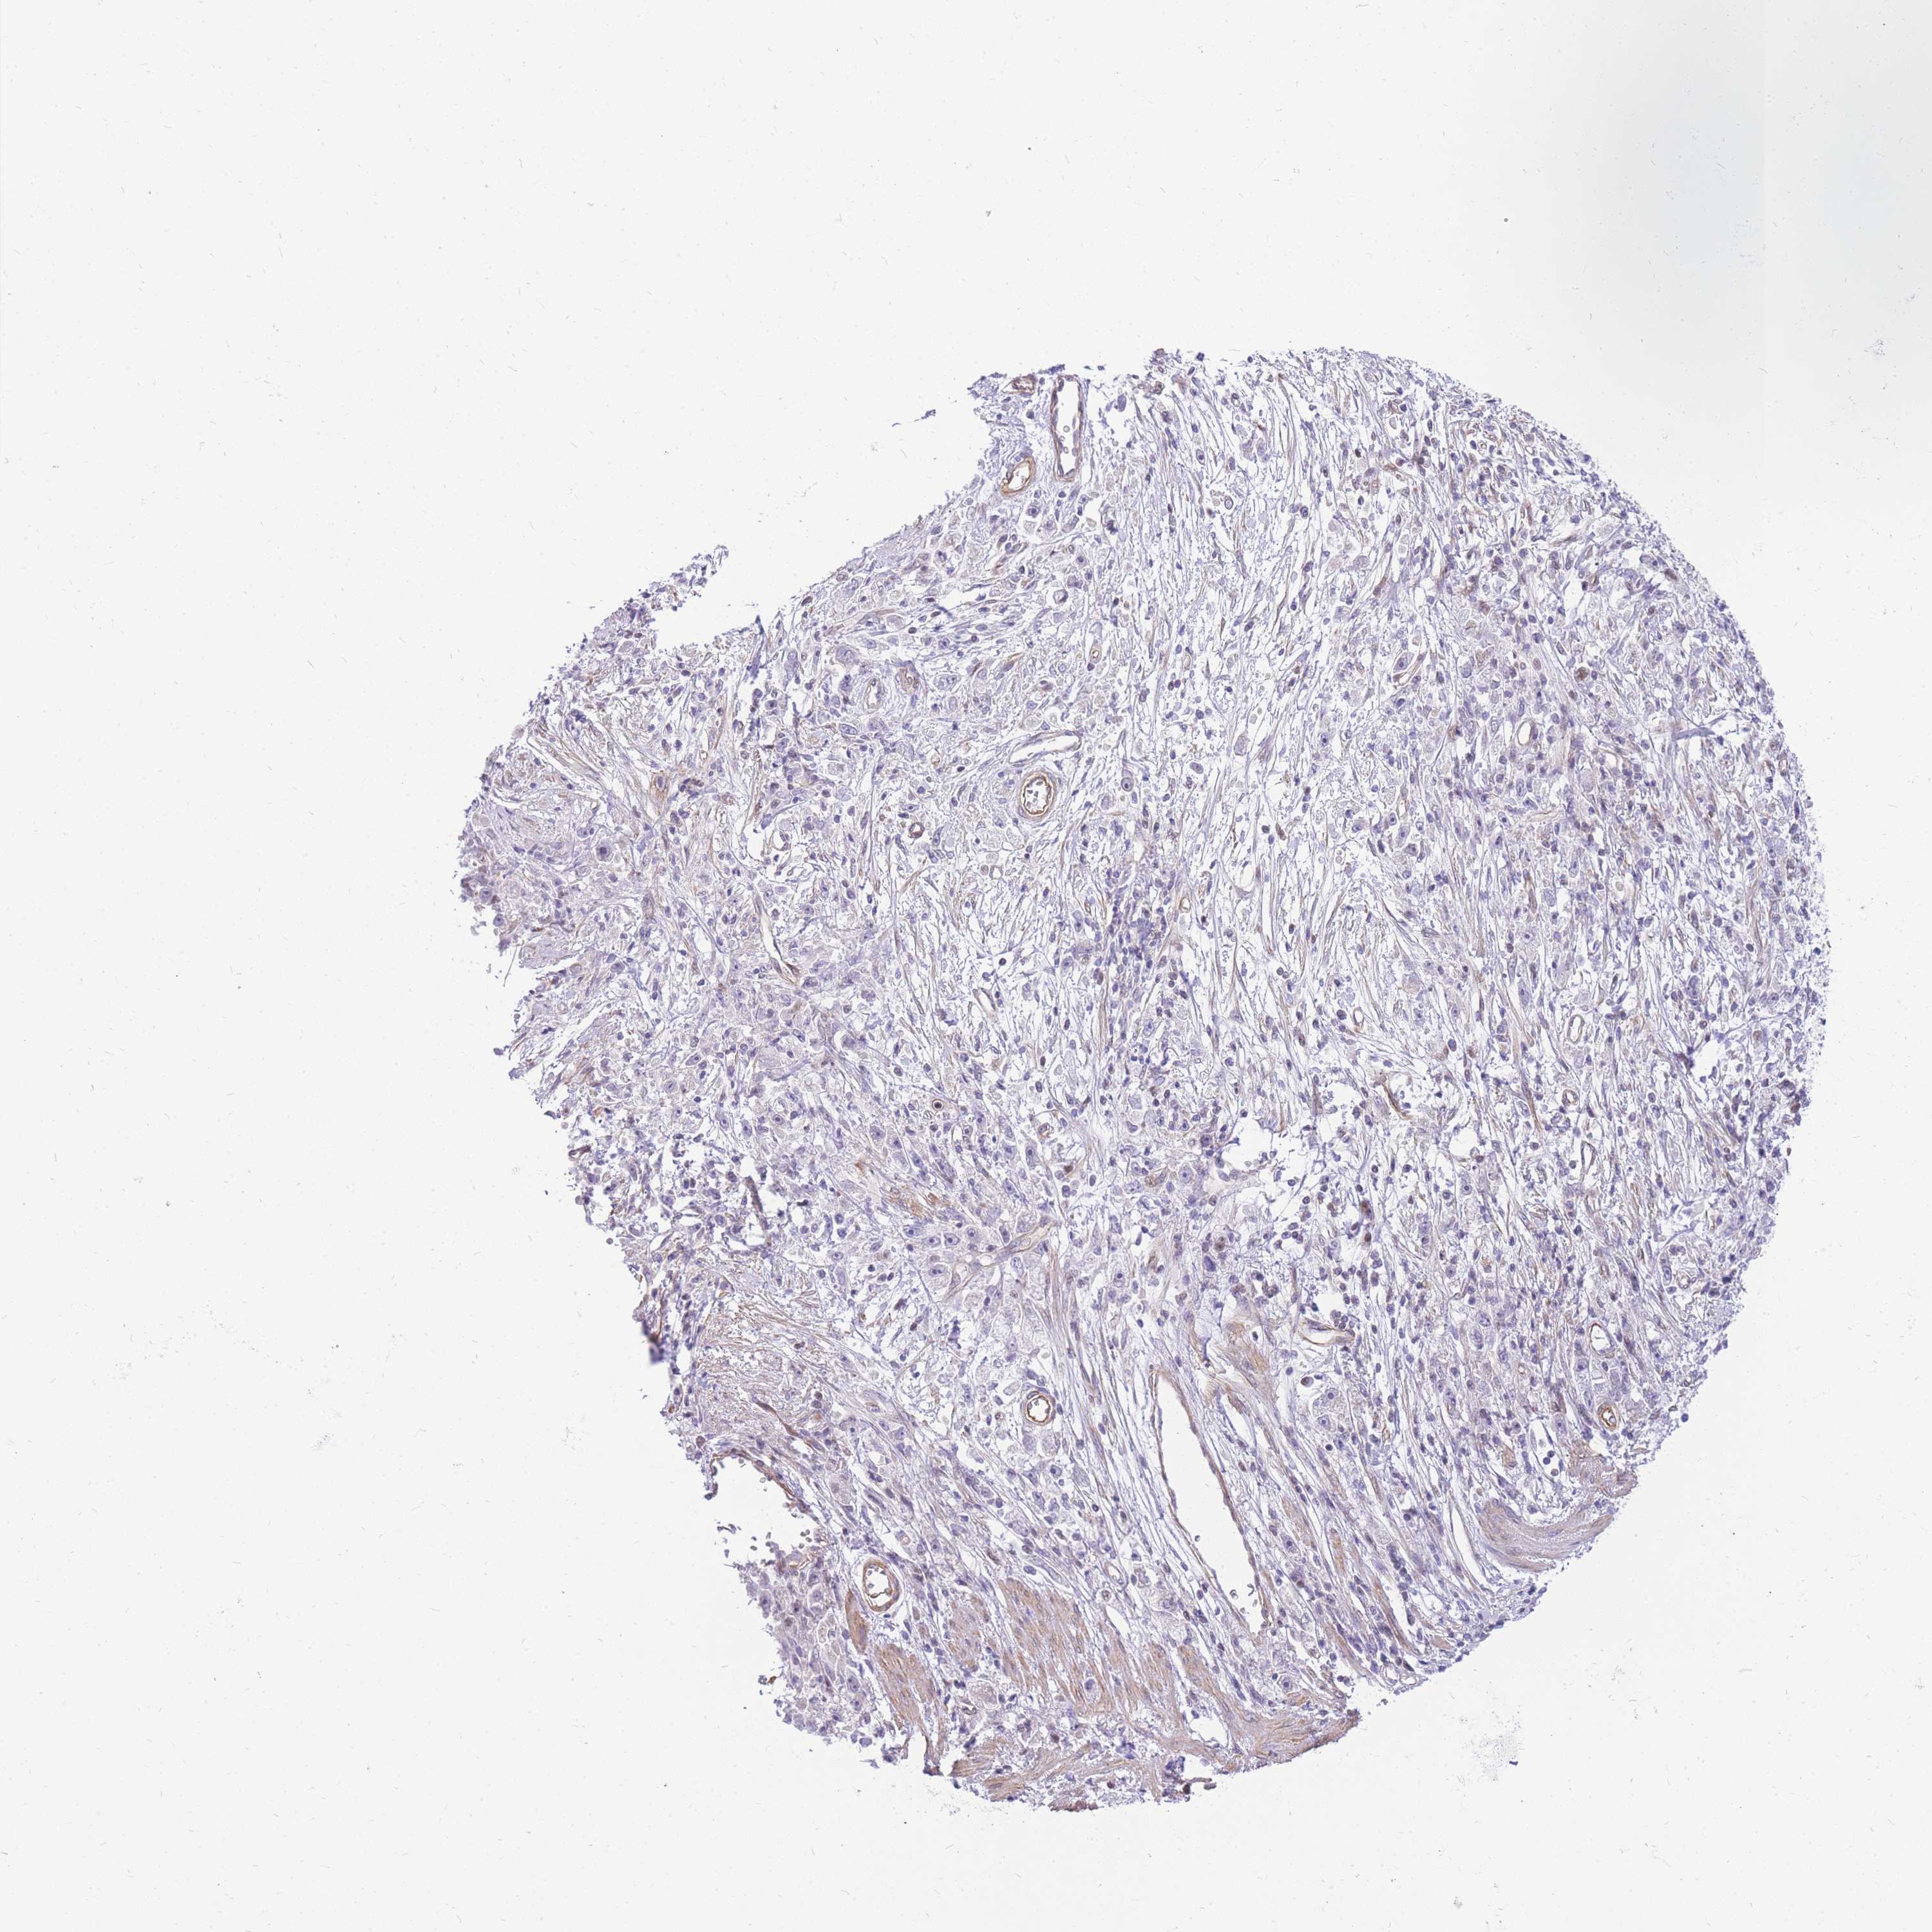

STOMACH CANCER - Protein expressioni

A mouse-over function shows sample information and annotation data. Click on an image to view it in a full screen mode. Samples can be filtered based on level of antibody staining by selecting one or several of the following categories: high, medium, low and not detected. The assay and annotation is described here.

Note that samples used for immunohistochemistry by the Human Protein Atlas do not correspond to samples in the TCGA dataset.

Antibody stainingi

Antibody staining in the annotated cell types in the current human tissue is reported as not detected, low, medium, or high, based on conventional immunohistochemistry profiling in selected tissues. This score is based on the combination of the staining intensity and fraction of stained cells.

Each image is clickable and will lead to virtual microscopy that enables deeper exploration of all samples and also displays staining intensity scores, fraction scores and subcellular localization as well as patient and tissue information for each sample.

Antibody HPA027242

Antibody HPA027328

Staining

High

Medium

Low

Not detected

Intensity

Strong

Moderate

Weak

Negative

Quantity

>75%

75%-25%

<25%

None

Location

Nuclear

Cytoplasmic/membranous

Cytoplasmic/membranous,nuclear

Adenocarcinoma, NOS